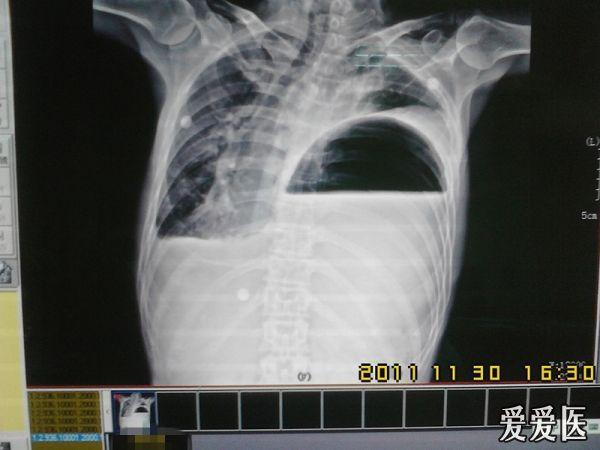

看到这张片子你会想到左侧膈疝

膈疝胸片

膈疝x线影像诊断

膈疝x线图片